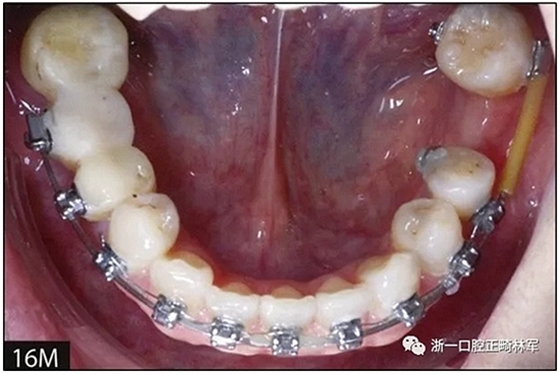

36歲;女性;尋求下頜左后方區(qū)域間隙管理的建議(圖1和圖2),通過(guò)治療獲得了良好的牙頜面效果(圖3和圖4)。她被診斷患有骨性I類和代償性牙性II類錯(cuò)合畸形,并且上頜左側(cè)尖牙缺失(圖1和2)。大約七年前,由于不可修復(fù)的齲齒,拔除了下頜左側(cè)第一和第二磨牙(圖5)。37相鄰的第三磨牙向近中移動(dòng)并傾斜入間隙,導(dǎo)致無(wú)牙頜間隙減小至約14 mm(圖2和圖5)。臨床和影像學(xué)評(píng)估顯示多發(fā)性齲損和在下頜右側(cè)567處有一不良的固定橋修復(fù)體(圖1和5)。此外,下頜左中切牙缺失,造成下頜中線向左側(cè)偏移約3 mm(圖1和圖2)?;颊咦栽V,她的右上第一前磨牙和左上尖牙在13歲時(shí)由其家庭牙醫(yī)拔除,因?yàn)樗鼈儽蛔枞筋a側(cè)萌出(圖1)。上頜第二磨牙缺失(未知病因),并且相鄰的第三磨牙已經(jīng)轉(zhuǎn)移到第二磨牙間隙中。如補(bǔ)充材料所示,美國(guó)正畸學(xué)差異指數(shù)DI是28分。種植體部位(下頜左側(cè)和右側(cè)第一磨牙)由于復(fù)雜性得到額外4分(補(bǔ)充材料)。

圖5. 治療前的側(cè)位片(上圖)和全景(下圖)的X光片